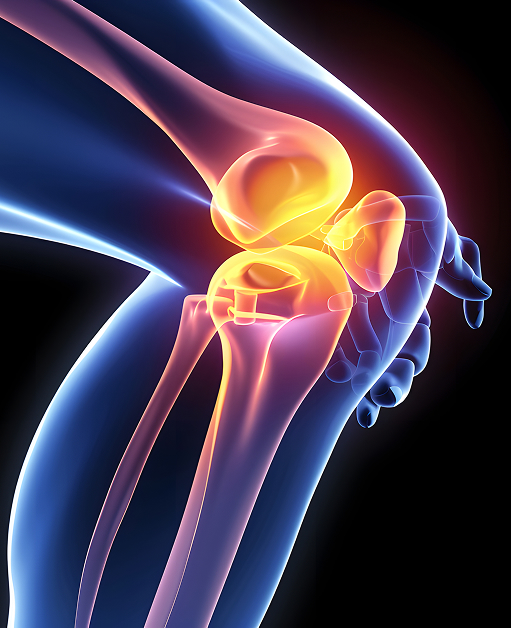

La structure de l’articulation du genou

L’articulation du genou relie la partie inférieure du fémur (os de la cuisse) à la partie supérieure du tibia (os de la jambe) et permet la flexion et l’extension de la jambe. Dans un genou sain, les surfaces de ces deux os — là où ils se rencontrent pour former l’articulation — sont recouvertes d’une couche de cartilage qui permet un glissement aisé et sans douleur.

Les ménisques sont des structures cartilagineuses en forme de croissant, solidement attachées au sommet du tibia, mais capables de se déplacer légèrement. Cette mobilité permet une petite rotation et un ajustement de l’articulation, tout en absorbant les charges progressives et soudaines exercées sur le genou.

La face postérieure de la rotule (ou patella) est également recouverte de cartilage et glisse dans une rainure située à l’avant du fémur. L’articulation est entourée d’une enveloppe de tissus mous appelée capsule articulaire, qui ferme l’articulation et produit un liquide synovial. Ce liquide nourrit, lubrifie et facilite le mouvement du genou.

L’articulation du genou est stabilisée par divers ligaments et tendons, qui la traversent ou la longent. La rotule elle-même contribue également à la stabilité et à la protection de l’articulation.